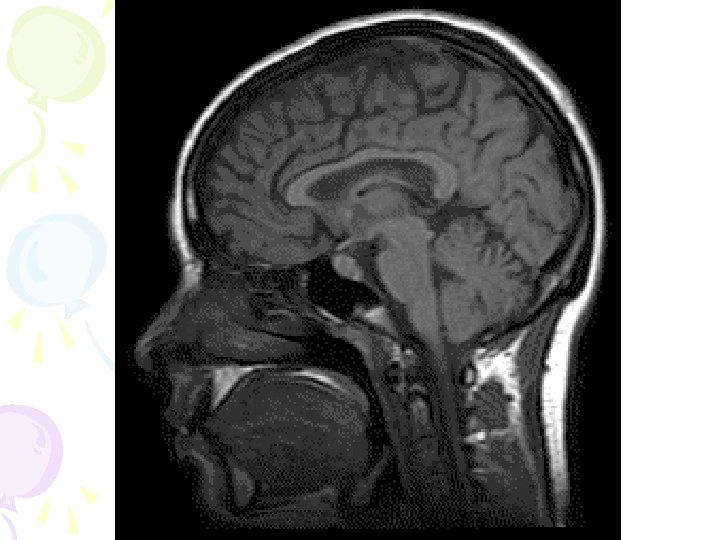

How do we know about the brain? • EEG- electrical activity • CAT- 3 D images • MRI- radio waves/Hydrogen atom energy • PET- chemical activity after injection of radioactive substance

Magnetic Resonance Imaging (MRI) • magnetic fields and radio waves images that allow us to see structures within the brain • More expensive, slower, BUT better at soft tissue and less harmful